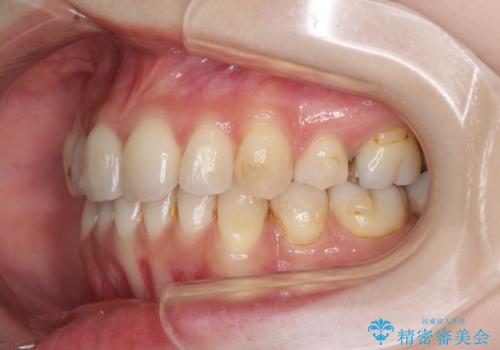

軽度な歯列不正 インビザライン・ライトによる矯正治療

- 上下前歯の叢生を気にして来院された患者様です。

費用を抑え、期間もあまりかけずに治療をしたいとのことで、インビザライン・ライトを用いて矯正治療を行うこととしました。